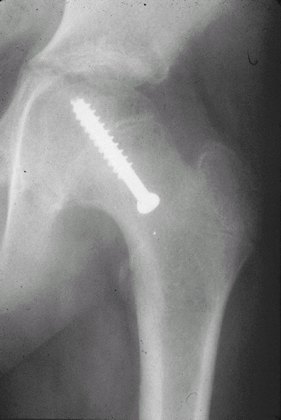

Fig. 4. In situ fixation of SCFE with 1 cannulated screw.

Surgery usually is done with 1 percutaneously placed screw to close the physis (Fig. 4).

1 guide pin is placed percutaneously from the anterior neck into the center of the femoral epiphysis.

An appropriate-length 6.5- or 7.3-mm cannulated screw is placed over the guide wire.